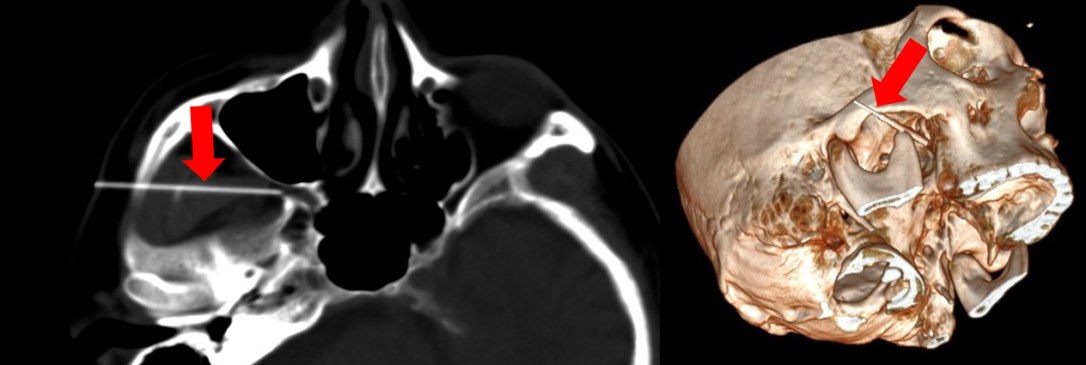

我們已經應用『電腦斷層與超音波即時同步化』這項導引技術到多位罹患頑固性三叉神經痛的病患,進行神經射頻燒灼術,並且成功地降低病患的三叉神經痛。由於這項技術能清楚地看見穿刺路徑上的血管(能避免穿刺血管後造成的臉部血腫),進而成功地導引針尖到三叉神經的顱底神經孔(能增加高頻神經熱凝療法的效用) (圖2)。我們相信,正確地使用這項技術能有效地減少病患的恐懼與操作醫師的擔憂,而讓更多的病患得到有效的治療。